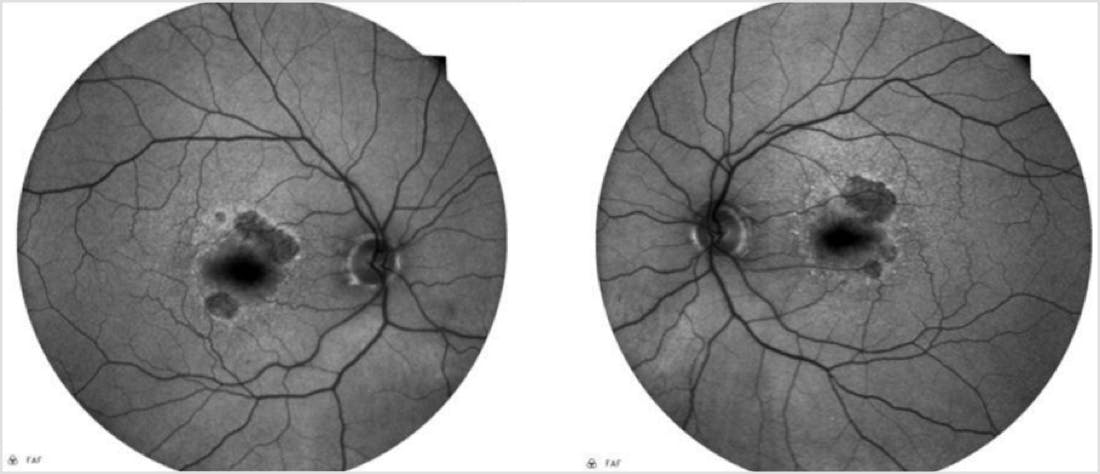

The patient’s BCVA was 20/25 bilaterally. Examination of the anterior segment revealed well centered posterior chamber IOLs with trace posterior capsular fibrosis in both eyes. Ophthalmoscopy revealed medium size drusen, mild RPE changes, and multiple areas of non-central geographic atrophy (GA) in both eyes. Color photography confirmed the clinical findings (Figure 1). Fundus autofluorescence (FAF) demonstrated well demarcated areas of parafoveal hypoautofluorescence consistent with GA. Additionally, these lesions had hyperautofluorescent borders, a known risk factor for progression (Figure 2). Optical coherence tomography (OCT) showed drusen, intraretinal hyperreflective foci, ellipsoid zone attenuation, early choroidal hypertransmission defects, and no evidence of intraretinal or subretinal fluid (Figure 3).

The patient was diagnosed with advanced non-exudative AMD with GA sparing the fovea. The pathogenesis and natural history were discussed in detail. His clinical exam and imaging showed multiple risk factors for GA progression, including multiple non-central lesions with hyperautofluorescent borders on FAF. The risks/benefits of referral for consideration of complement inhibition therapy were discussed. The patient opted for a referral to a retina specialist. A follow-up exam in our clinic at 6 months was also scheduled, knowing that there was some potential for treatment to not be recommended for his GA, as it had been just a few months since FDA-approved treatment was available. In addition, the need to monitor for progression of his posterior capsular opacity was noted.

This case is notable for several reasons. First, it shows the utility of multimodal imaging, and in particular, the use of FAF imaging for monitoring patients with GA. Note that in Figure 1, it is difficult to appreciate the borders of the GA lesion, whereas in Figure 2, clearly evident are hypoautofluorescent areas (indicating areas of already dead retinal pigment epithelium) and hyperautofluorescent areas (indicating areas of potential expansion of the GA lesion). Meanwhile, the OCT image in Figure 3 helped support the diagnosis of GA while also demonstrating key signs of potential progression. With the benefit of serial imaging captured at the follow-up visit (Figure 5), it was possible to detect progression of this patient’s GA despite stable visual acuity and no change on clinical examination.